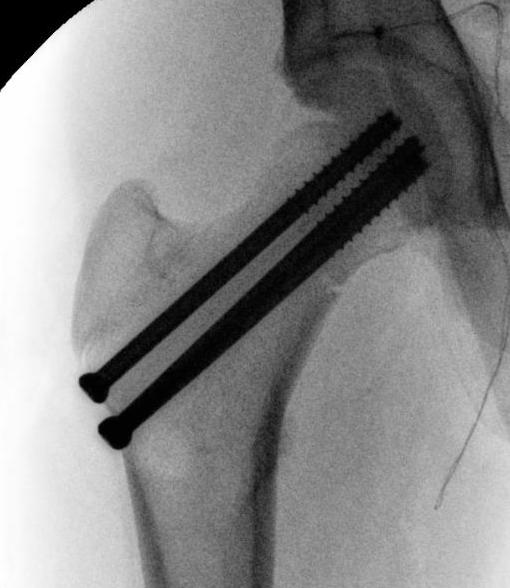

Displaced

Closed reduction

- < 3 years K wires

- > 3 cannulated screws / pediatic hip screw

Spica post op < 10 years